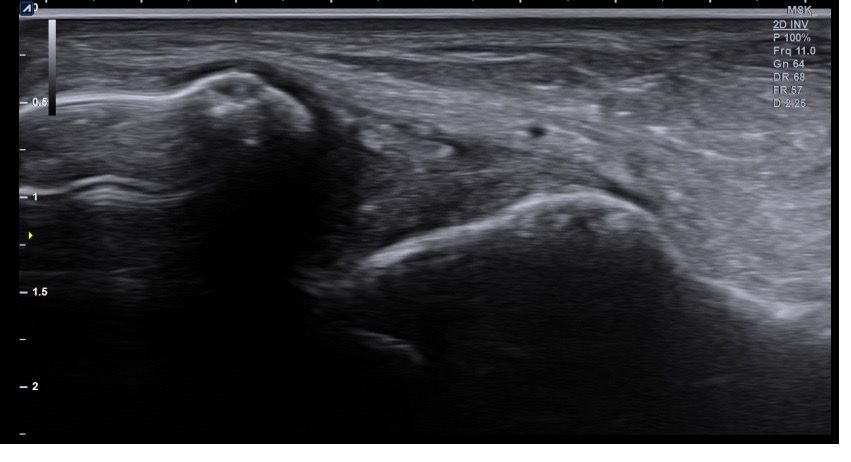

복숭아뼈 미세골절 초음파 사진 관련 질문

발목 접지른 후 치료받는 중인데요 복숭아뼈 미세골절이라고 하셨네요 3월 1일 다친뒤네 3월7일 병원방문후에 위에 초음파랑 엑스레이 촬영했고요 그뒤 반깁스 중입니다. 위에 엑스레이 상에선 안나오는데 초음파 사진에선 미세골절이 맞을까요? 골절이 경미한 수준인지 아니면 중한 건지 궁금합니다 그리고 다음주에 병원 방문 후 초음파 또 촬영하기로 했는데 그때 반깁스도 풀 수 있을까요??

미세골절 같은 경우 엑스레이서 잘 안 보일 수 있고 초음파에서 연부조직과 뼈의 상태를 좀 더 세밀하게 확인하여 확인할 수 있습니다. 미세골절이 경미한 수준이라면 초음파를 통해서 확인이 가능하며 치료 진행 상황에 따라 반깁스를 푸는 시점은 달라질수 있습니다.

미세골절은 엑스레이에서 잘 보이지 않을 수 있고 초음파에서는 연조직과 뼈의 상태를 좀 더 세밀하게 확인할 수 있습니다. 미세골절이 경미한 수준이라면 초음파에서 확인할 수 있지만 치료 진행 상황에 따라 반깁스를 풀수 있는 시점이 달라질 수 있습니다! 병원 방문 시 초음파 결과를 방탕으로 치료 계획을 조정하게 되고 전문가가 판단하는 시점에 맞춰 반깁스를 풀 수 있습니다!

발목의 복숭아뼈에 미세골절이 의심되는 경우, 엑스레이에서는 미세골절이 잘 보이지 않을 수 있습니다. 엑스레이는 큰 골절을 잘 확인하지만, 미세한 골절이나 염증 반응은 잘 나타나지 않기 때문이죠. 초음파는 조직의 변화를 보다 민감하게 감지할 수 있기 때문에, 미세골절을 발견하는 데 도움을 줄 수 있습니다. 초음파에서 미세골절이 확인되었다면, 이는 경미한 골절일 가능성이 높아요. 하지만 골절의 정확한 상태나 치유 과정을 판단하려면 정밀 검사가 필요하죠